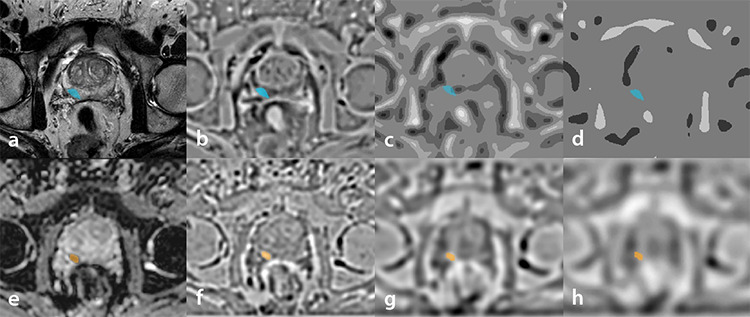

Methods: MRI images of patients who were diagnosed with cancer with histopathological confirmation following prostate MRI were collected retrospectively. Patients with a Gleason score of 3+3 were considered to have clinically ciPCa, and patients with a Gleason score of 3+4 and above were considered to have csPCa. Radiomics features were extracted from T2-weighted (T2W) images, apparent diffusion coefficient (ADC) images, and their corresponding Laplacian of Gaussian (LoG) filtered versions. Additionally, a third feature subset was created by combining the T2W and ADC images, enhancing the analysis with an integrated approach. Once the features were extracted, Pearson’s correlation coefficient and selection were performed using wrapper-based sequential algorithms. The models were then built using support vector machine (SVM) and logistic regression (LR) machine learning algorithms. The models were validated using a five-fold cross-validation technique.

Results: This study included 77 patients, 30 with ciPCA and 47 with csPCA. From each image, four images were extracted with LoG filtering, and 111 features were obtained from each image. After feature selection, 5 features were obtained from T2W images, 5 from ADC images, and 15 from the combined dataset. In the SVM model, area under the curve (AUC) values of 0.64 for T2W, 0.86 for ADC, and 0.86 for the combined dataset were obtained in the test set. In the LR model, AUC values of 0.79 for T2W, 0.86 for ADC, and 0.85 for the combined dataset were obtained.